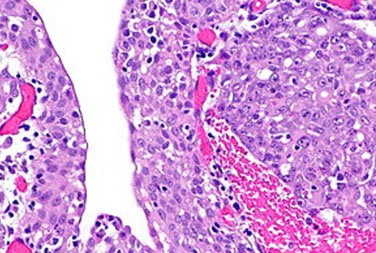

Focal Segmental Glomerulosclerosis (FSGS)

term that has no specific meaning, is more of a label given to many non-specific entities, and should not be used as a dx; causes non-selective proteinuria

- usually in juxtamedullary glomeruli first

MCC nephrotic syndrome in black adults (~1/3 cases)

(?membranous MC overall nephrotic syndrome?)

- MC glomerular dz in HIV pts

-- more severe in HIV pts, blacks, IVDUs, sickle cell pts

- may not be well-represented 2/2 sampling error (can mistake for MCD if affected glomeruli not sampled)

- pathogenesis may be related to soluble urokinase plasminogen activating receptor (suPAR) and injury occurs in glom epithelial cell or podocyte

- glomerular stress (hyperfiltration) may be important in secondary forms (obesity, dec renal function); is not an IC dz

Causes: renal agenesis, HIV, IVDU, reflux nephropathy

Genes: Apolipoprotein L! (APOL1) mutations in blacks may help c sleeping sickness, but predisposes to FSGS

LM: segmental sclerosis and hyalinosis (NO immune complexes) of glomerular capillary segments in some but not all gloms (thus, focal)

-usualy occurs on tip near prox tubule

IF: neg or nonspecific IgM and C3 accumulation in sclerotic segments

EM: No deposits; in sclerotic areas, non-specific segmental collapse of GBM, inc mesangial matrix and dep of hyaline material; also widespread foot process effacement

Collapsing Glomerulopathy

Assoc c HIV, blacks, IVDU, but can be 2/2 other causes (pamidronate tx), glomerular loops look like they have been sucked dry, c hypertrophy of glomerular epithelial cells that fill Bowman's space and separate collapsed glomerular tufts

On low power, has some abnormal tubules, which are dilated c casts, c inc cytoplasmic granularity

- glomeruli have collapse of capillary loops c vacuolated granular visceral epithelial cells on outside of collapsed tufts c material similar to tubular casts in Bowman's space

EM: tubulo-reticular bodies (agg of intracytoplasmic tubular structures in the ER)